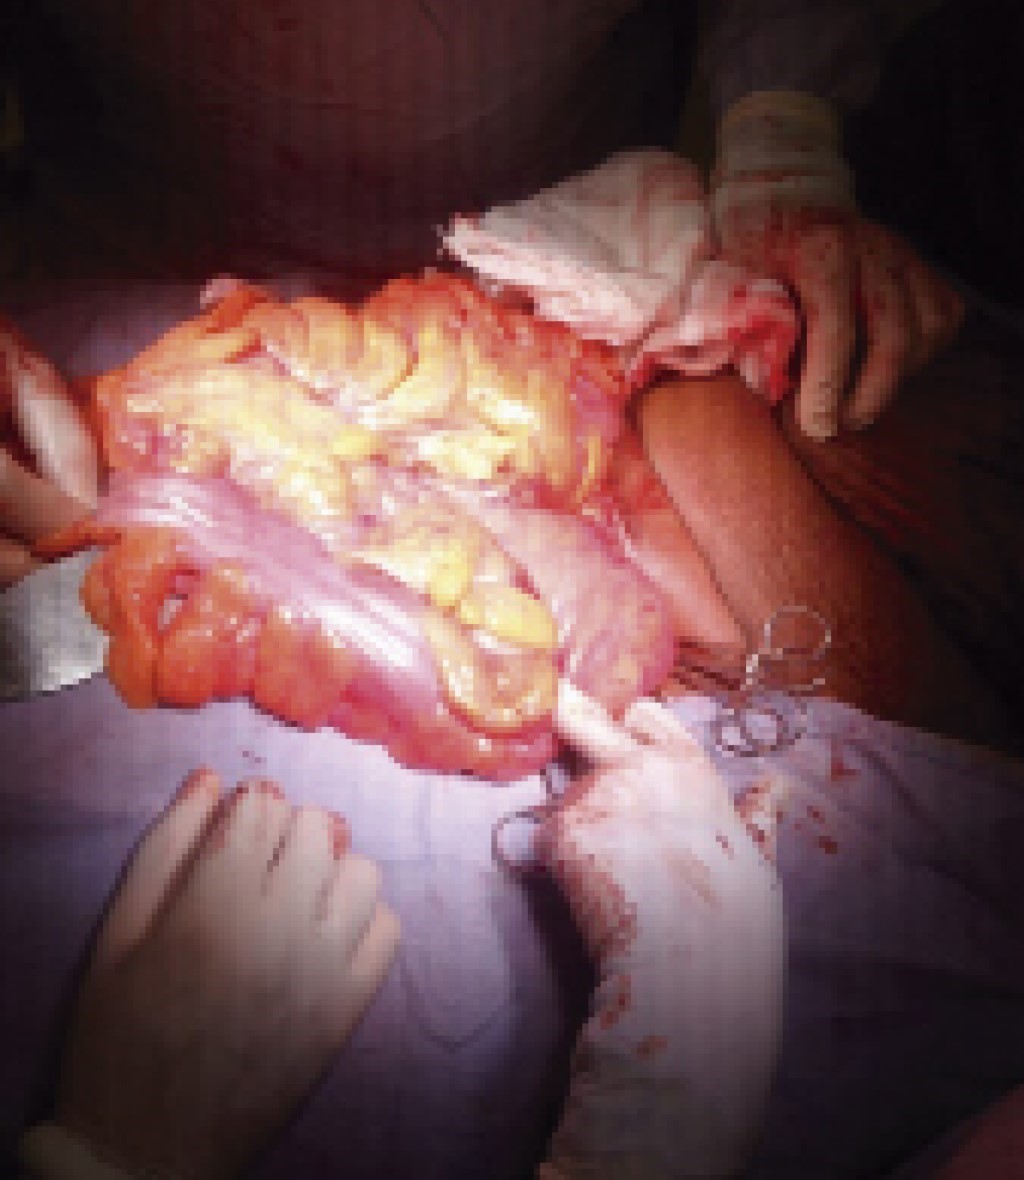

Under regional anesthesia, a left inguinal approach was performed through a standard transverse incision. A direct hernial sac was identified, dissected, and separated from the spermatic cord. After opening the hernia sac, small bowel loops, sigmoid colon, and omentum were identified (Figures 2, 3 and 4), which were manually introduced into the abdominal cavity without difficulty. The anatomical defect was repaired according to the Lichtenstein technique; there were no restrictive pulmonary changes during the transoperative and postoperative periods. The patient was discharged on the fourth day of hospital stay due to improvement. There was no hernia recurrence after clinical and ultrasound follow-ups for 1.5 years (Figure 5). The patient reports that his quality of life has improved notably, increasing his personal and sexual relationships.

Figure 2

Figure 3

Figure 4